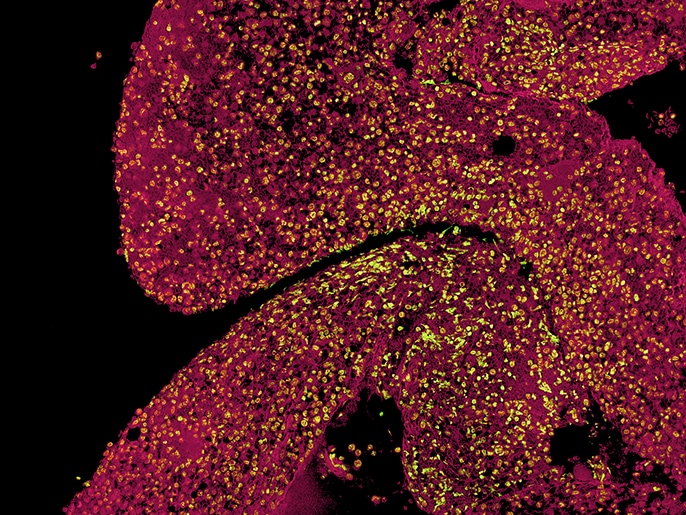

ガッターマン博士らは、鉄とポルフィリンがうまく結合しない原因を探るため、ミトコンドリアの内膜やマトリックスでのタンパク質間相互作用について研究を進めているという。蛍光顕微鏡BZシリーズを使って、タンパク質間相互作用をPLA(近接ライゲーションアッセイ)で蛍光シグナルとして可視化することで、膜複合体に構造異常がないか調べているのだ。またセクショニング機能を使えば、蛍光ボケのない鮮明な画像が得られる。焦点が合った平面からの信号のみが抽出され、フルフォーカスの画像を作成できる。研究対象のタンパク質間相互作用には、フェロケラターゼと「ミトコンドリアのヘム代謝複合体」の相互作用パートナーが関わっており、そのうちの一部は一過性のものである。

骨髄前駆細胞の挙動を再現して理解するために、ガッターマン博士とその作業グループは現在、研究室内で三次元細胞培養技術を確立している。これまでは、通常の二次元コロニー形成アッセイを行っていた。これは、造血前駆細胞が半固体の培地の中でコロニーを形成し、その状態で研究できる方法である。しかし、三次元細胞培養によって顕微鏡への要求はさらに高まり、蛍光顕微鏡BZシリーズのZスタック機能や画像連結機能、セクショニング機能が真価を発揮するようになってきた。これらの機能が蛍光顕微鏡BZシリーズ導入の決め手となったのである。ガッターマン博士らは、三次元細胞培養における免疫組織化学や核染色、DNA-RNAハイブリッド構造の検出などの用途に向けて、まったく新しい可視化方法を開発している。